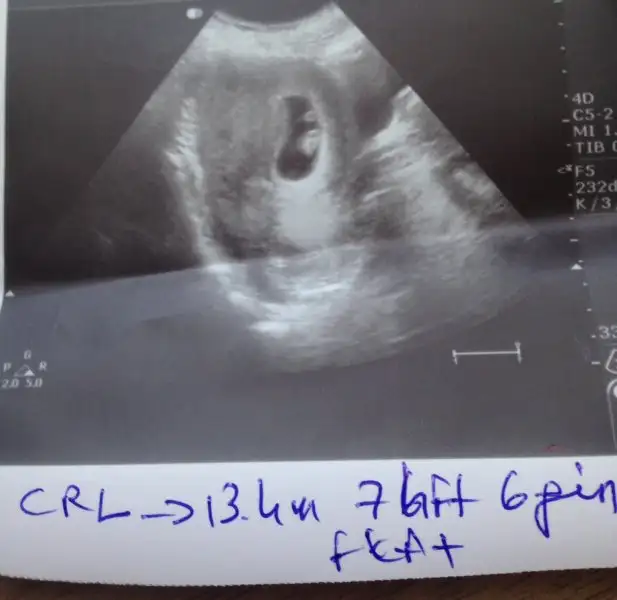

Merhaba bir de bunu yorumlayabilir misiniz plesanta yönüne göre 6 hafta 4 günlükUltrason vajinalse erkek abdominalse kız gibi

kızMerhaba bir de bunu yorumlayabilir misiniz plesanta yönüne göre 6 hafta 4 günlük

Vajinalse erkek gibi abdominalse kiz gibiMerhaba bir de bunu yorumlayabilir misiniz plesanta yönüne göre 6 hafta 4 günlük